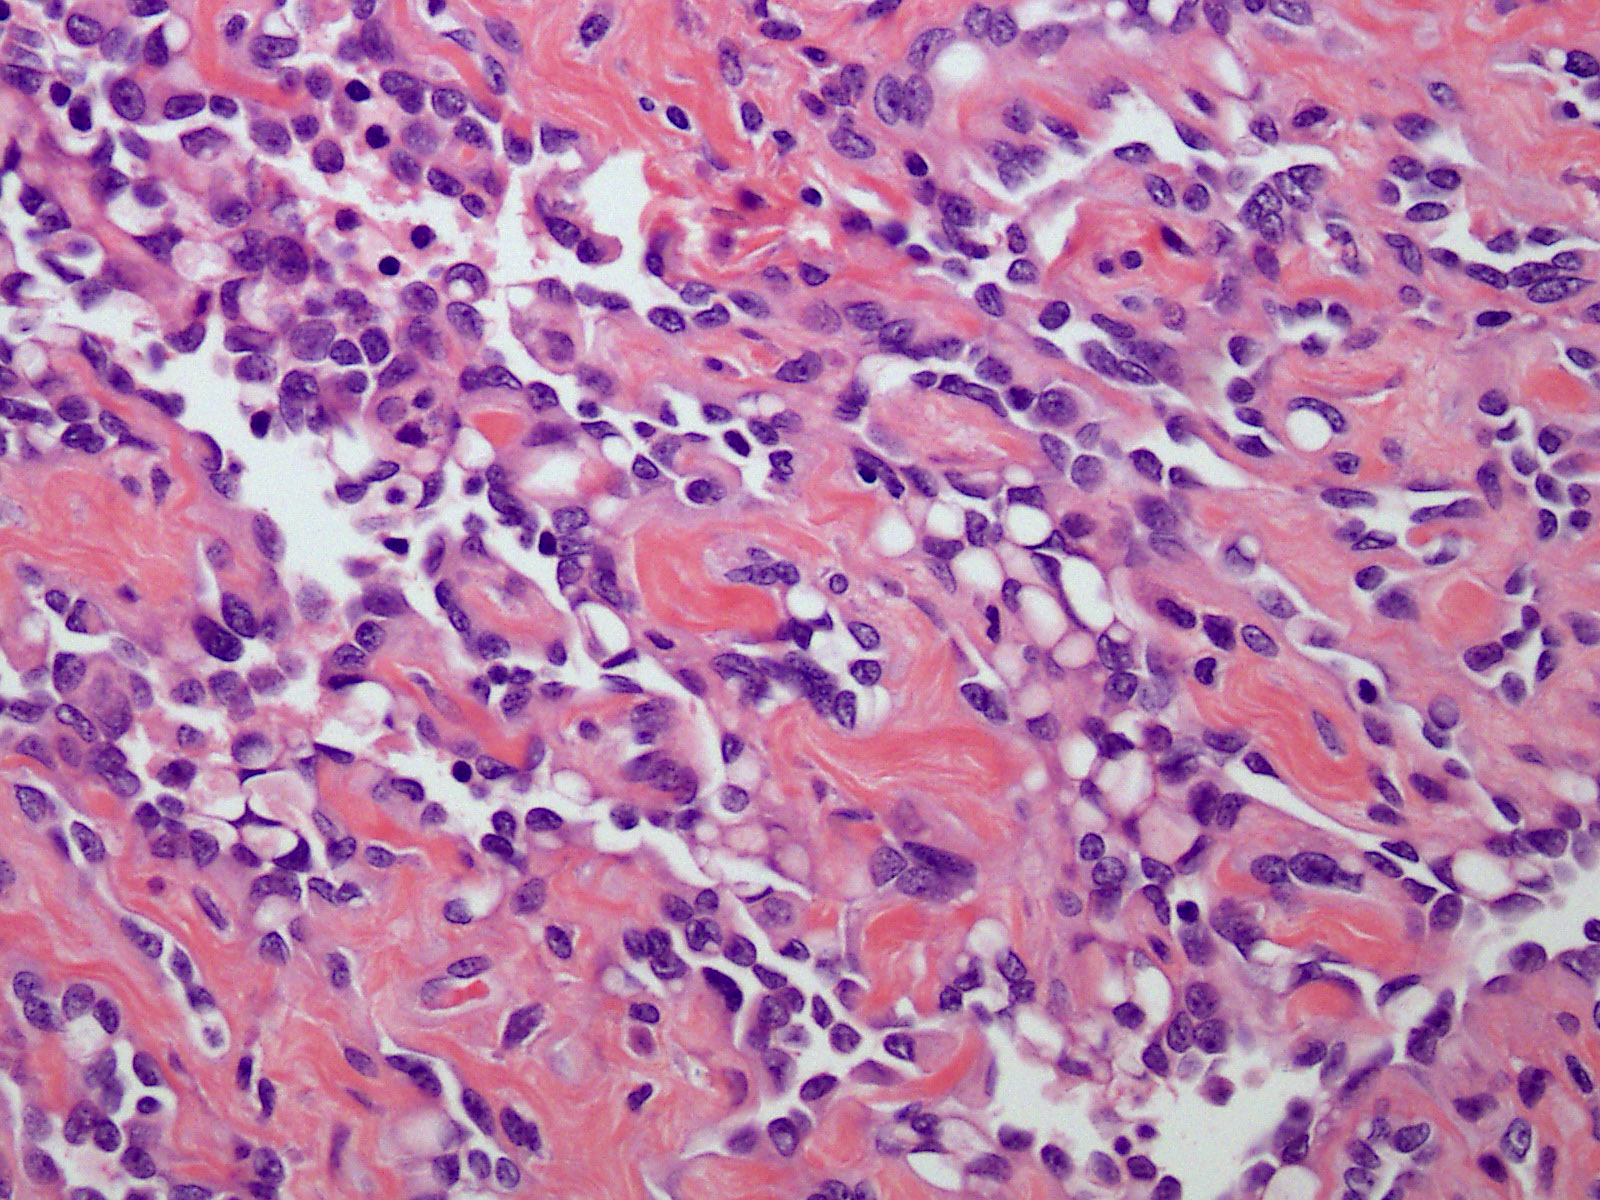

Microscopic (histologic) description

- Poorly circumscribed lesion, infiltrating dermis and subcutis with dissecting planes (Int J Clin Exp Pathol 2010;3:528)

- Composed of elongated arborizing vascular channels that resemble rete testis, hence the name

- Endothelial cells are bland with hobnailed hyperchromatic nuclei

- Nuclear atypia is not seen

- Mitotic figures are rare

- Lesional stroma is fibrotic and shows lymphoid infiltrate (J Med Case Rep 2021;15:69, Int J Clin Exp Pathol 2010;3:528)

- Occasional solid growth may be seen (Stockman: Diagnostic Pathology - Vascular, 1st Edition, 2015)

- In the dermis, vessels may become ectatic and lose retiform appearance

- Occasional cells with cytoplasmic lumina may be rarely seen (J Med Case Rep 2021;15:69)

- Occasionally, intraluminal papillary proliferation may be seen, resembling Dabska tumor (Hornick: Practical Soft Tissue Pathology - A Diagnostic Approach, 2nd Edition, 2018)

Microscopic (histologic) images